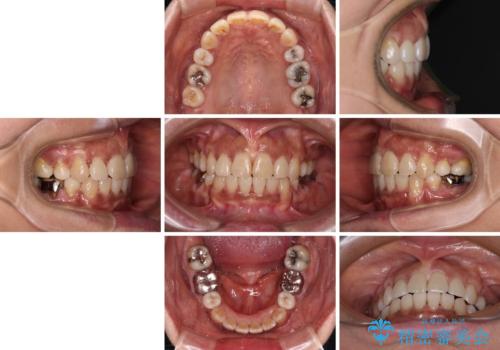

- 審美装置

- 2年4ヶ月

- 10-30回

- 八重歯やクロスバイトを気にして来院された患者様です。

口元の突出感はありませんでしたが、デコボコが強く、非抜歯矯正とすると出っ歯仕上がりとなる可能性があったため、上下左右の第一小臼歯4本を抜歯し、ワイヤー装置にて矯正治療を行うこととしました。

抜歯矯正により口元が引っ込みすぎて、ほうれい線が顕著となるのではないかと心配しておりましたが、矯正後にほうれい線が気になることはなく、口元もすっきりとした感じになりました。